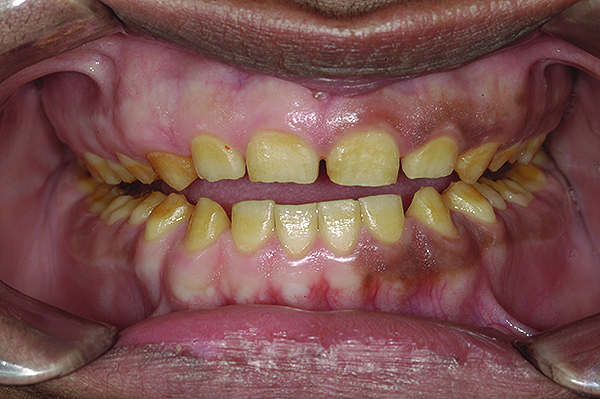

The authors report on a 21-year-old patient who presented with severe discoloration and mild sensitivity of teeth (Figure 1). The teeth visible in his smile were very short, unsightly, and unbecoming for his age.

A thorough clinical examination and analysis were carried out to assess the esthetic and functional problems of the patient (Figure 2 through Figure 7). The medical history was non-contributory, except for mild leukoderma. Temporomandibular joint (TMJ) function was within normal range.

Mounted study casts were used to evaluate occlusion. The relevant findings were as follows2: Facial analysis revealed a canted maxillary occlusal plane and canted dental midline. Dentolabial analysis showed that the maxillary incisors were not adequately visible during repose; it also revealed a reverse smile line, as well as a wide smile showing 12 teeth. Results from the phonetic analysis were that “F” and “V” sounds revealed upper incisal shortening, “M” and “S” pronunciation disclosed a diminished vertical dimension of occlusion (VDO), and “E” sounds showed severe shortening of incisors. Dental analysis revealed thick biotype, asymmetry and inappropriate location of gingival levels and zenith, incorrect axial inclinations, a displeasing width-to-length ratio, and pitted surfaces on most teeth. Interproximal decay was evident on several posterior teeth, as revealed by radiographic analysis. Finally, occlusal examination indicated discrepancy between maximum intercuspation (MIP) and centric relation (CR) as well as a lack of anterior guidance/posterior disclusion.

Figure 5. Preoperative 1:1 retracted frontal view.

Figure 5